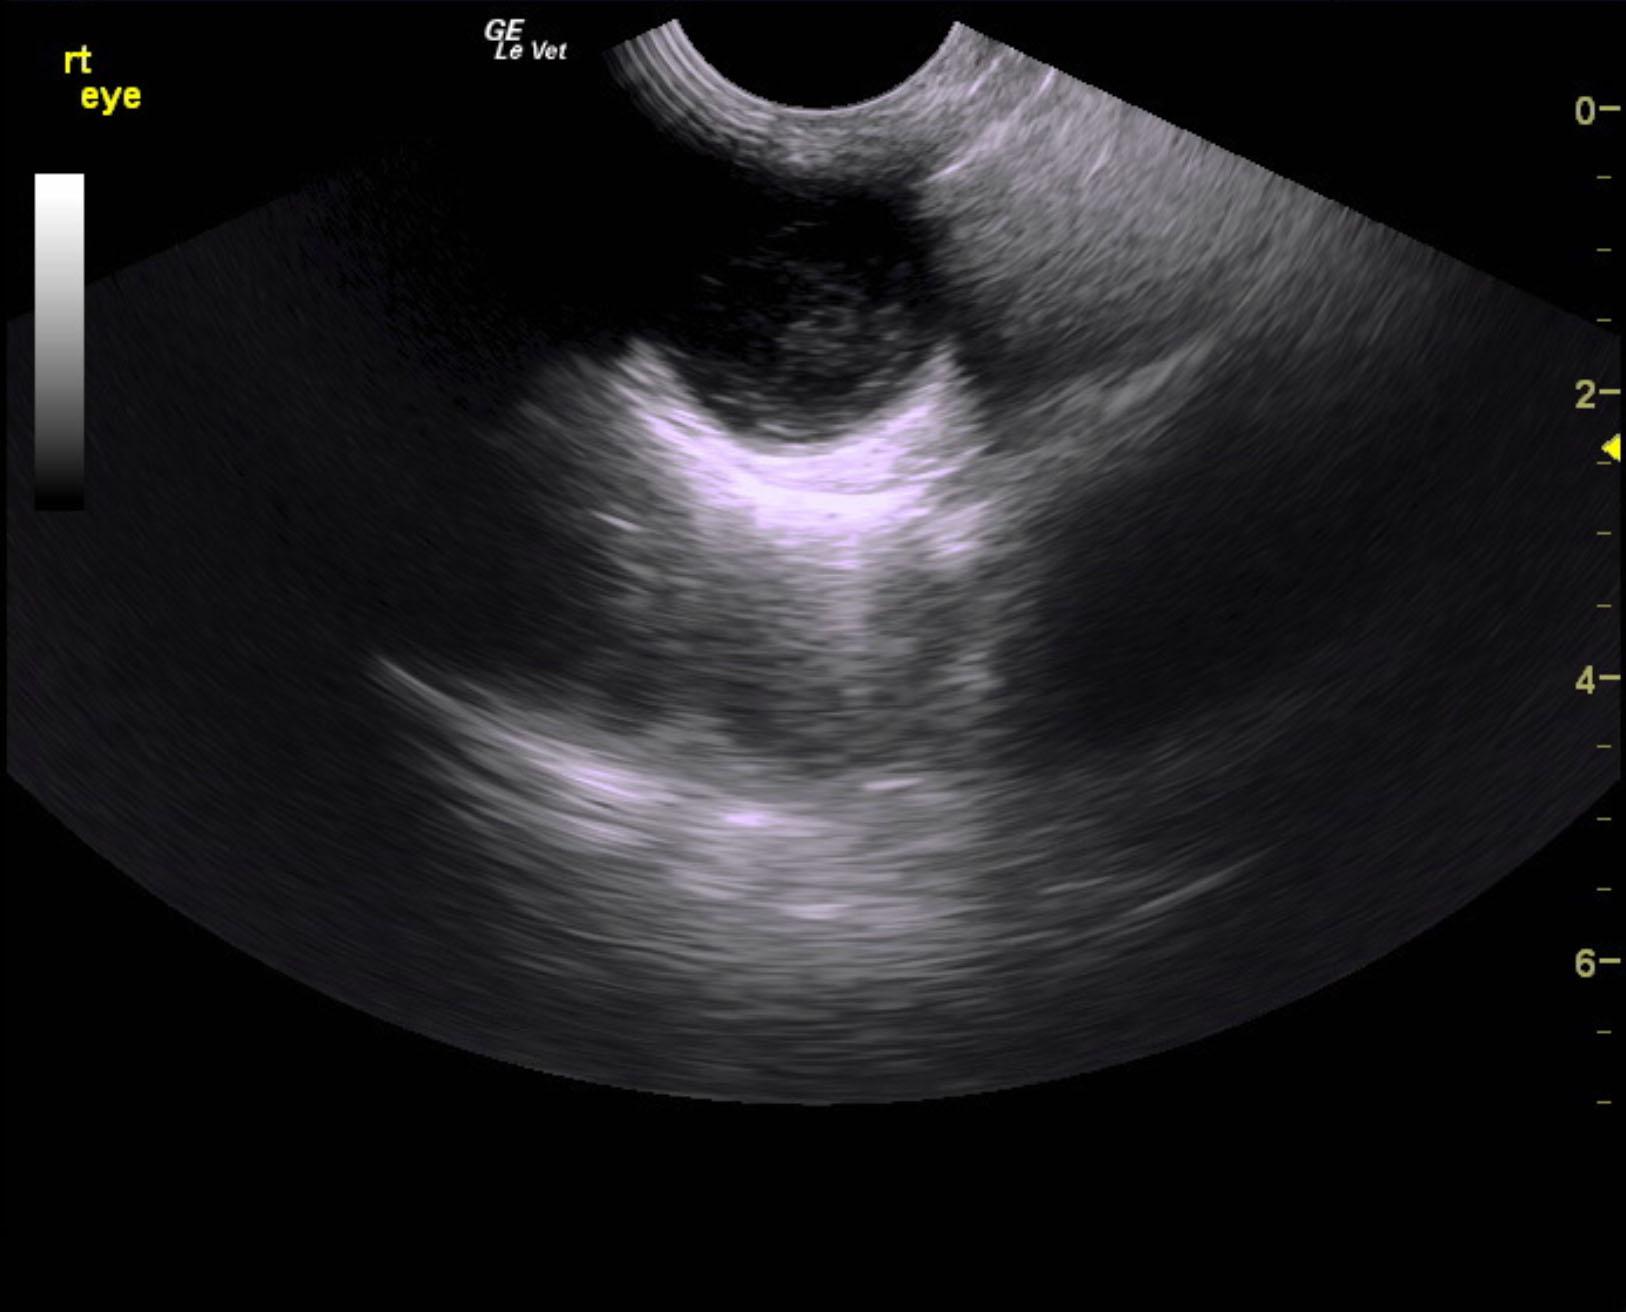

An 11-year-old NM Schnauzer was presented for evaluation of a possible eye tumor and splenic mass. On physical examination, left ocular pressure was increased. CBC showed mild anemia and on survey radiographs possible splenic mass and bladder stones were evident.